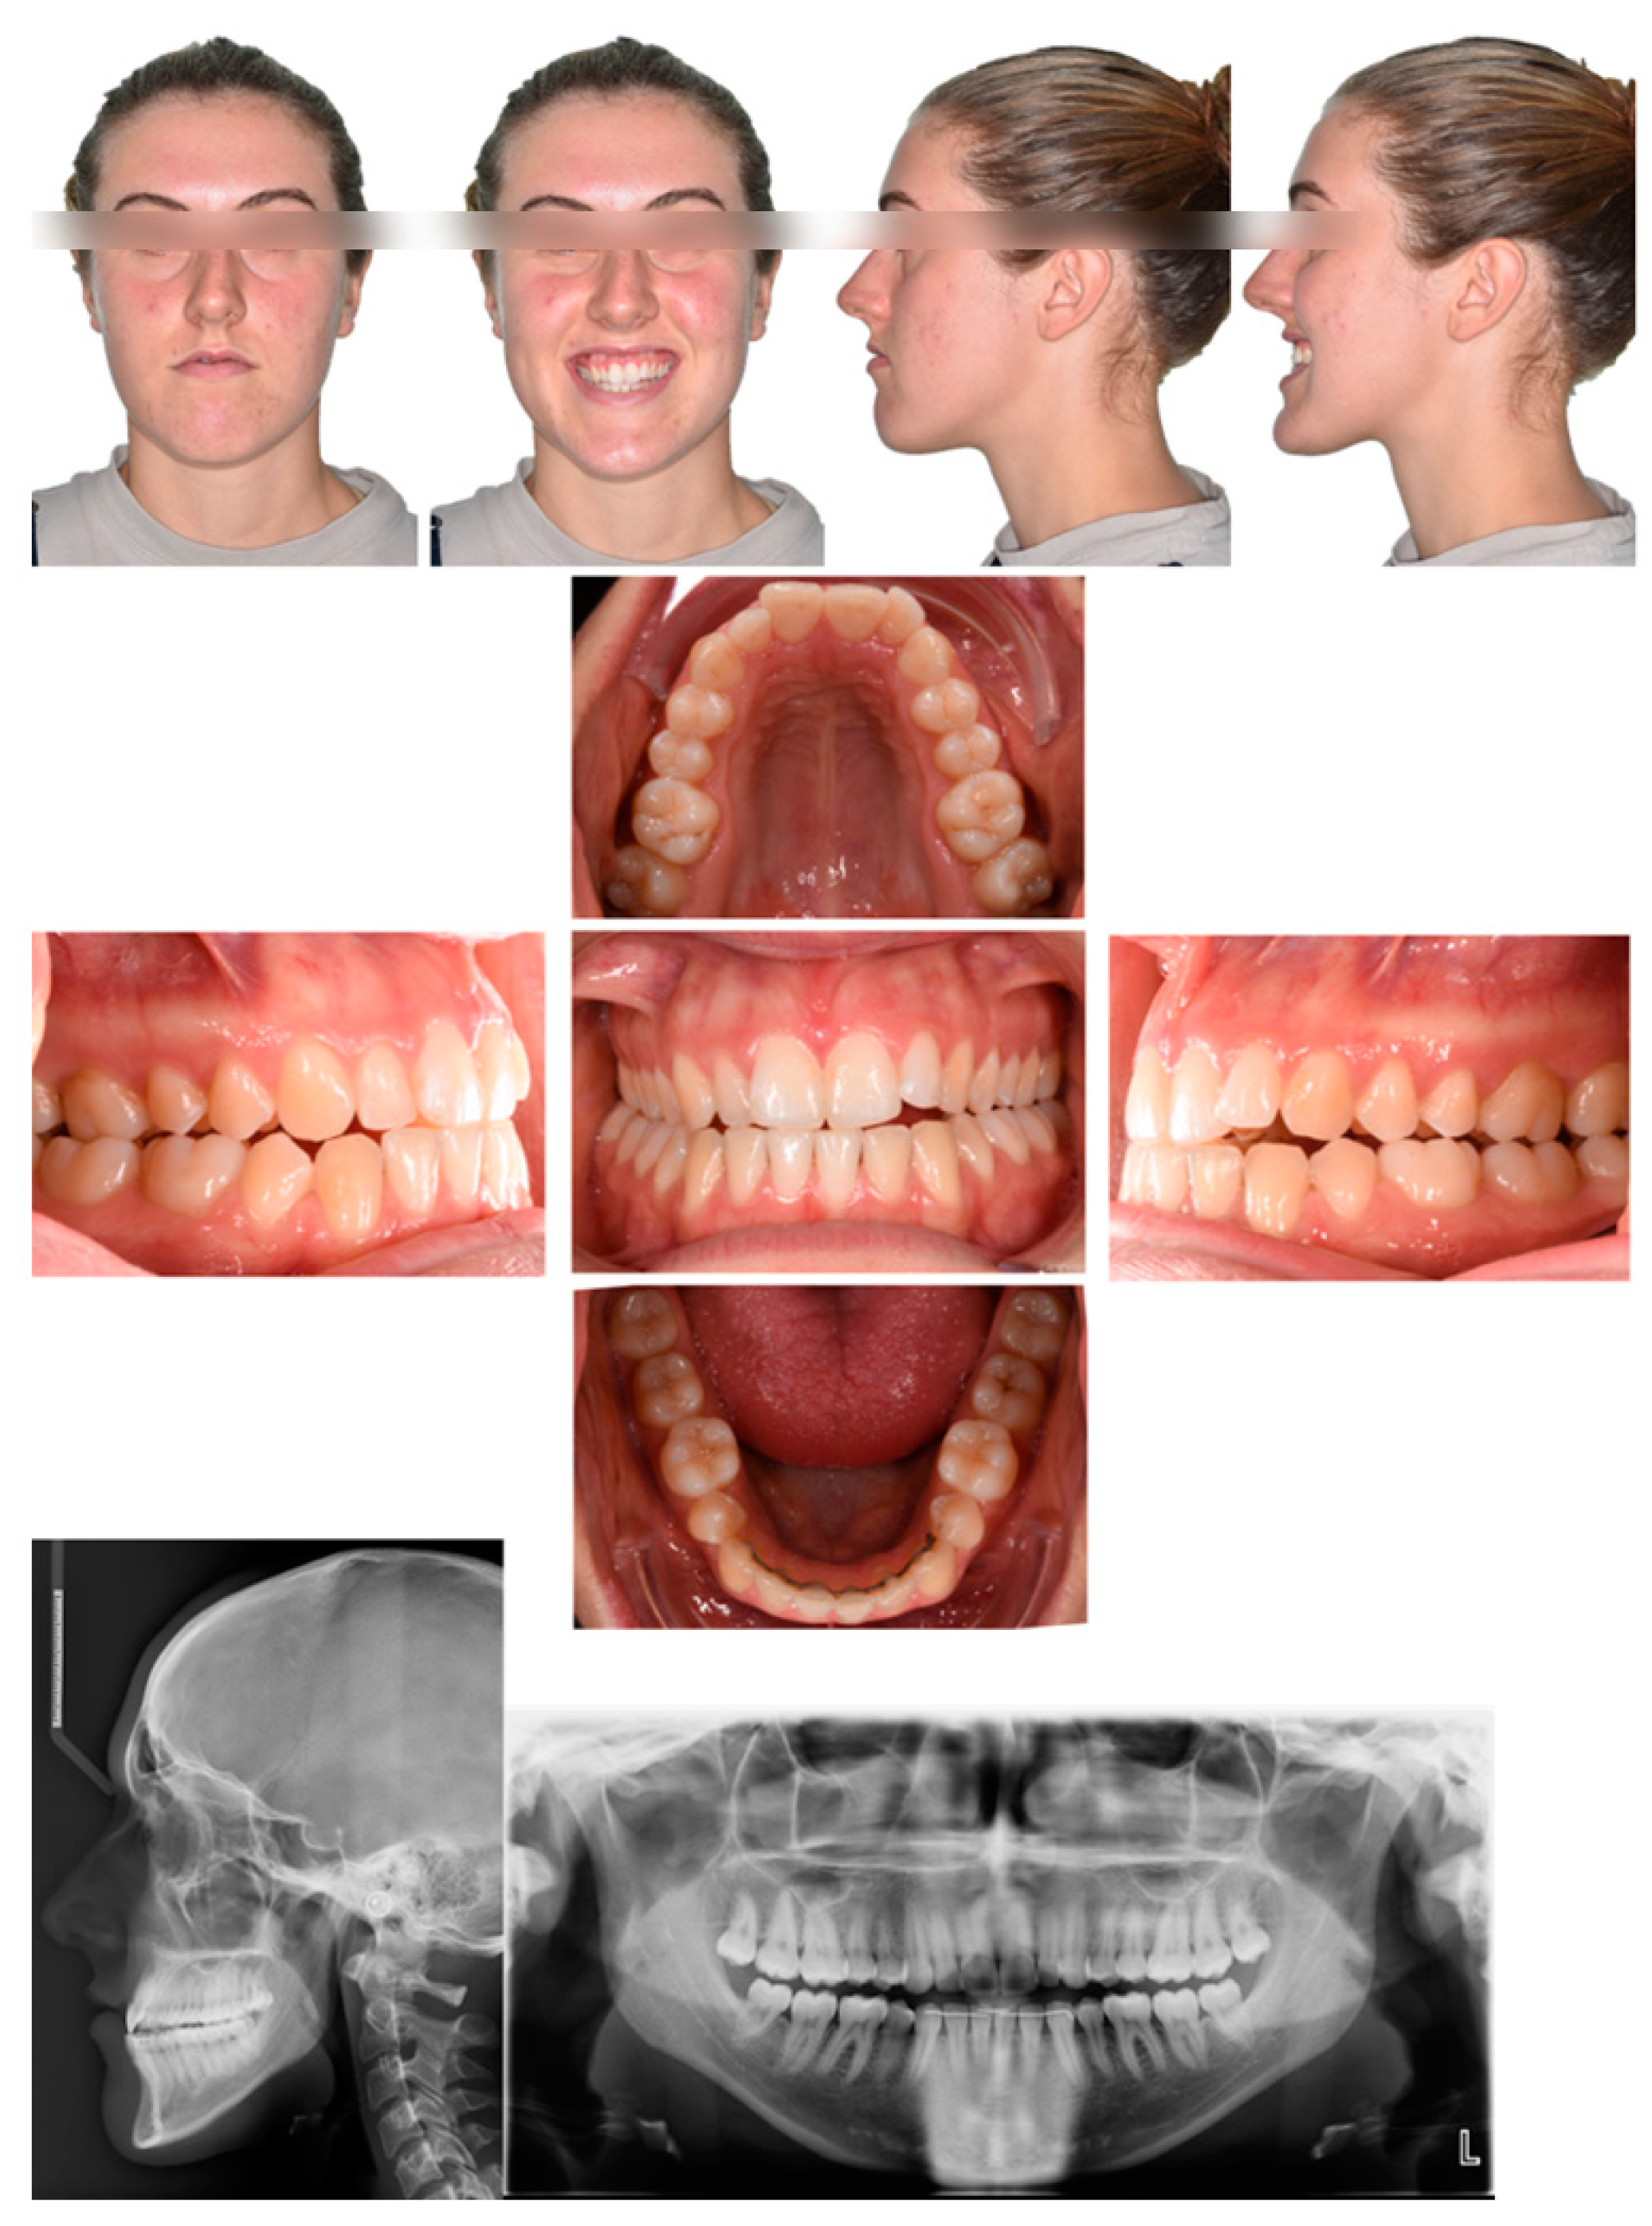

2.1. Diagnosis and Individual Treatment Planning

2.4. Post-Operative Orthodontic Phase

3. Objective Assessment and Quality of Life Evaluation